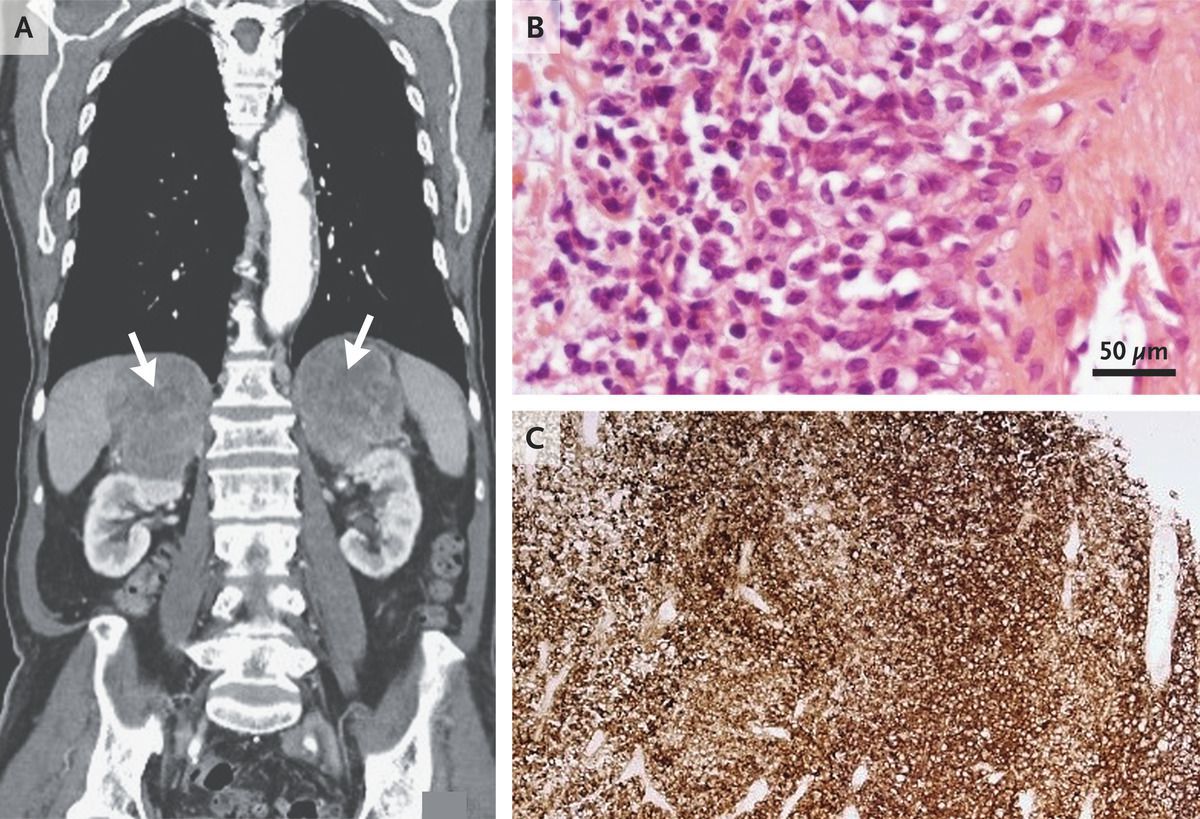

An 83-year-old man with coronary artery disease, hypertension, and hyperlipidemia presented to the emergency department with a 6-week history of fatigue, loss of appetite, and weight loss. His blood pressure was 115/80 mm Hg while he was seated but dropped to 95/65 mm Hg after he stood up. Laboratory studies were notable for a sodium level of 130 mmol per liter (reference range, 133 to 146) and a potassium level of 5.6 mmol per liter (reference range, 3.5 to 5.3). Cosyntropin stimulation testing showed an inadequate peak cortisol level; the corticotropin level was elevated at 87 ng per liter (reference range, 7 to 63). After the patient began treatment with hydrocortisone and fludrocortisone, his energy and appetite improved, and his electrolyte levels normalized. Computed tomography of the abdomen revealed marked enlargement of both adrenal glands, each of which measured more than 9 cm in greatest dimension, without lymphadenopathy (Panel A, arrows). After confirmation of normal plasma metanephrine levels, an adrenal biopsy was performed, which revealed high-grade B-cell lymphoma. Hematoxylin and eosin staining showed nuclear pleomorphism (Panel B), and immunohistochemical staining for the B-cell marker CD20 was positive (Panel C). Primary adrenal lymphoma is rare. It typically occurs in both adrenal glands and may be associated with adrenal insufficiency, as in this case. Chemotherapy was initiated, and the patient was doing well after 3 months.